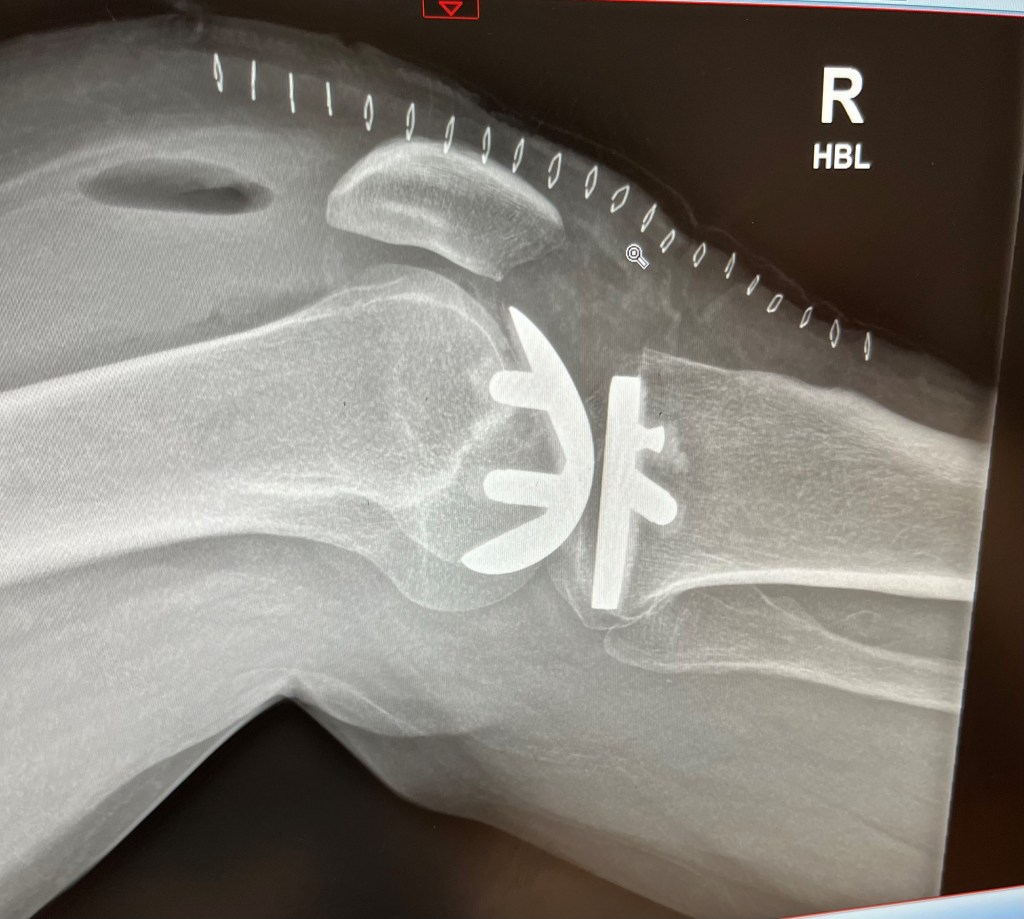

The surgeon was unimpressed when I went to see him within 6 weeks of the cartilage op, telling me that I hadn’t given it enough time to work. When I reminded him that I was living with incurable cancer and time was actually quite important, he relented and scheduled me for a part knee replacement on 1st May which went ahead as planned and I’m now bionic!

Recovery has been way tougher than expected. The knee itself is great but the loss of cardio vascular fitness had a huge impact and I’ve really struggled to get fitness back. It’s very much still a work in progress but I’m very determined!